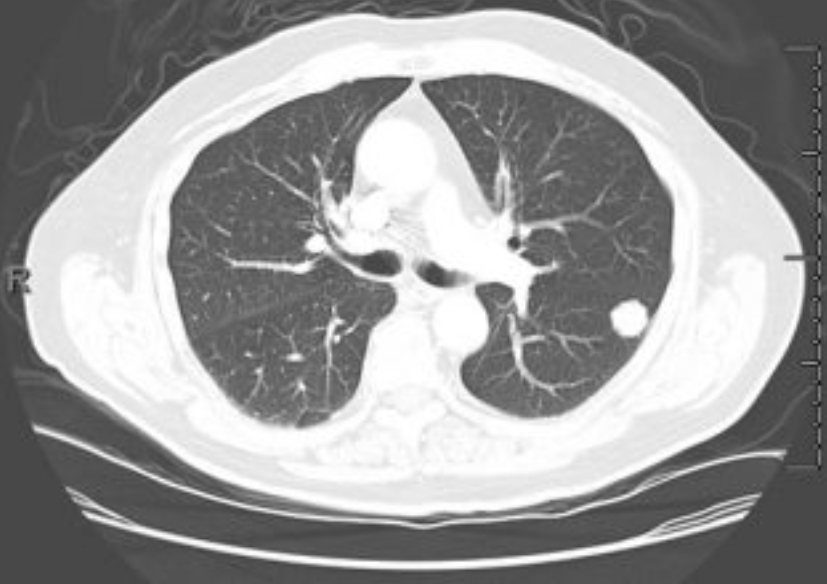

폐 편평세포암

폐 편평세포암은 폐암의 한 유형으로, 주로 흡연과 관련이 있습니다. 기침이 3주 이상 지속되거나 피 섞인 가래, 숨이 차는 증상이 있으면 검사를 받아야 합니다. 흡연자는 비흡연자보다 편평세포암 발생 위험이 몇 배나 높습니다. 금연은 가장 강력한 예방책이며, 폐 건강을 지키는 가장 직접적인 방법입니다.

진단은 흉부 X선, CT, 기관지 내시경, 조직검사로 이뤄집니다. 치료는 수술, 방사선, 항암치료, 면역치료가 병합됩니다. 최근에는 맞춤형 치료제가 도입되어 생존율이 향상되고 있습니다.